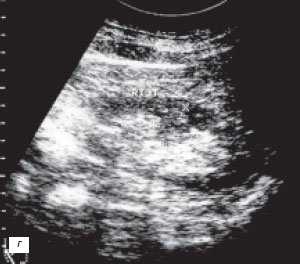

(Слева) УЗИ, продольная плоскость сканирования: гипоэхогенное «объемное образование» в центре, которое выступает в почечную лоханку.

(Справа) КТ с контрастированием, аксиальная проекция: у этого же пациента установлено, что «объемное образование» — это нормальное корковое вещество почки, которое инвагинирует в почечную лоханку между чашечками верхнего полюса и меж полюсной областью почки. Обратите внимание на нормальный внешний контур почки. Бертиниевы колонны чаще всего выявляют с одной стороны и слева, как в данном случае: в 18% случаев они могут быть двусторонними.